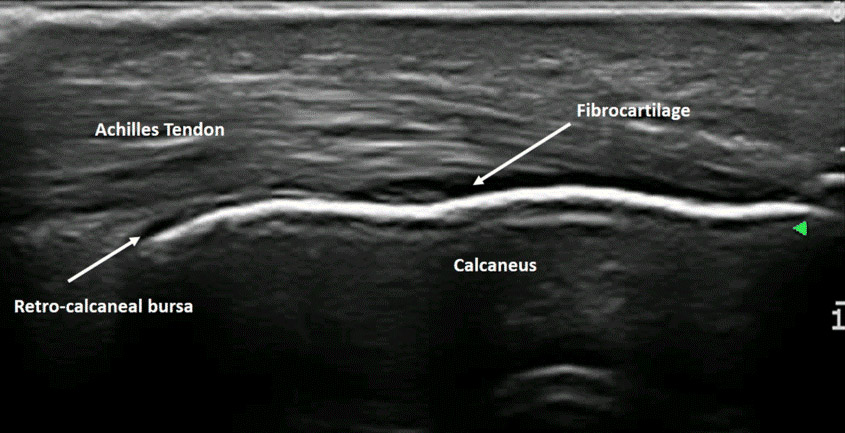

Ultrasound can be used to diagnose a variety of MSK injuries and disorders.

Focused ultrasound imaging has proven to be a useful and cost-efficient tool to many providers when diagnosing and treating their patients. MSK imaging is

primarily used to evaluate traumatic, inflammatory, and degenerative conditions of structures. When superficial imaging is required, ultrasound can

achieve extremely high resolution, quite comparable to that of MRI or CT scanning. It identifies damage or problems in joints, tendons, ligaments, muscles

and nerves where the patient has pain. The ability to provide a dynamic component while evaluating MSK structures gives light to injuries that could otherwise

not be seen.

MSK ultrasound provides dynamic information. Scans can be performed while moving the joint through a range of motion. Ultrasound imaging can help identify:

• Tendinosis/Tendinitis

• Tendon and ligament tears

• Bursitis (inflammation or fluid within the bursa)